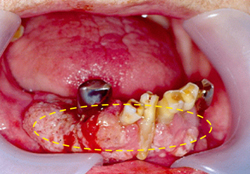

이 부위도 초기에는 잇몸에 발생한 염증이나 양성 종양과 유사하게 보일 수 있습니다. 진행되면 잇몸 주변의 치아를 둘러싸고 있는 치조골을 침범하기 때문에 치아가 흔들리게 됩니다. 더 진행하면 턱뼈를 침범하며 입술의 감각도 둔하게 됩니다. 간혹 치아를 뽑고 나서 상처가 아물지 않고 한 달 이상 지속적인 염증이 생기는 경우가 있습니다. 이러한 경우에는 잇몸에 발생한 구강암일 가능성도 있기 때문에 정밀한 검사를 받아보시는 것이 좋습니다.

[아래 잇몸에 발생한 구강암]